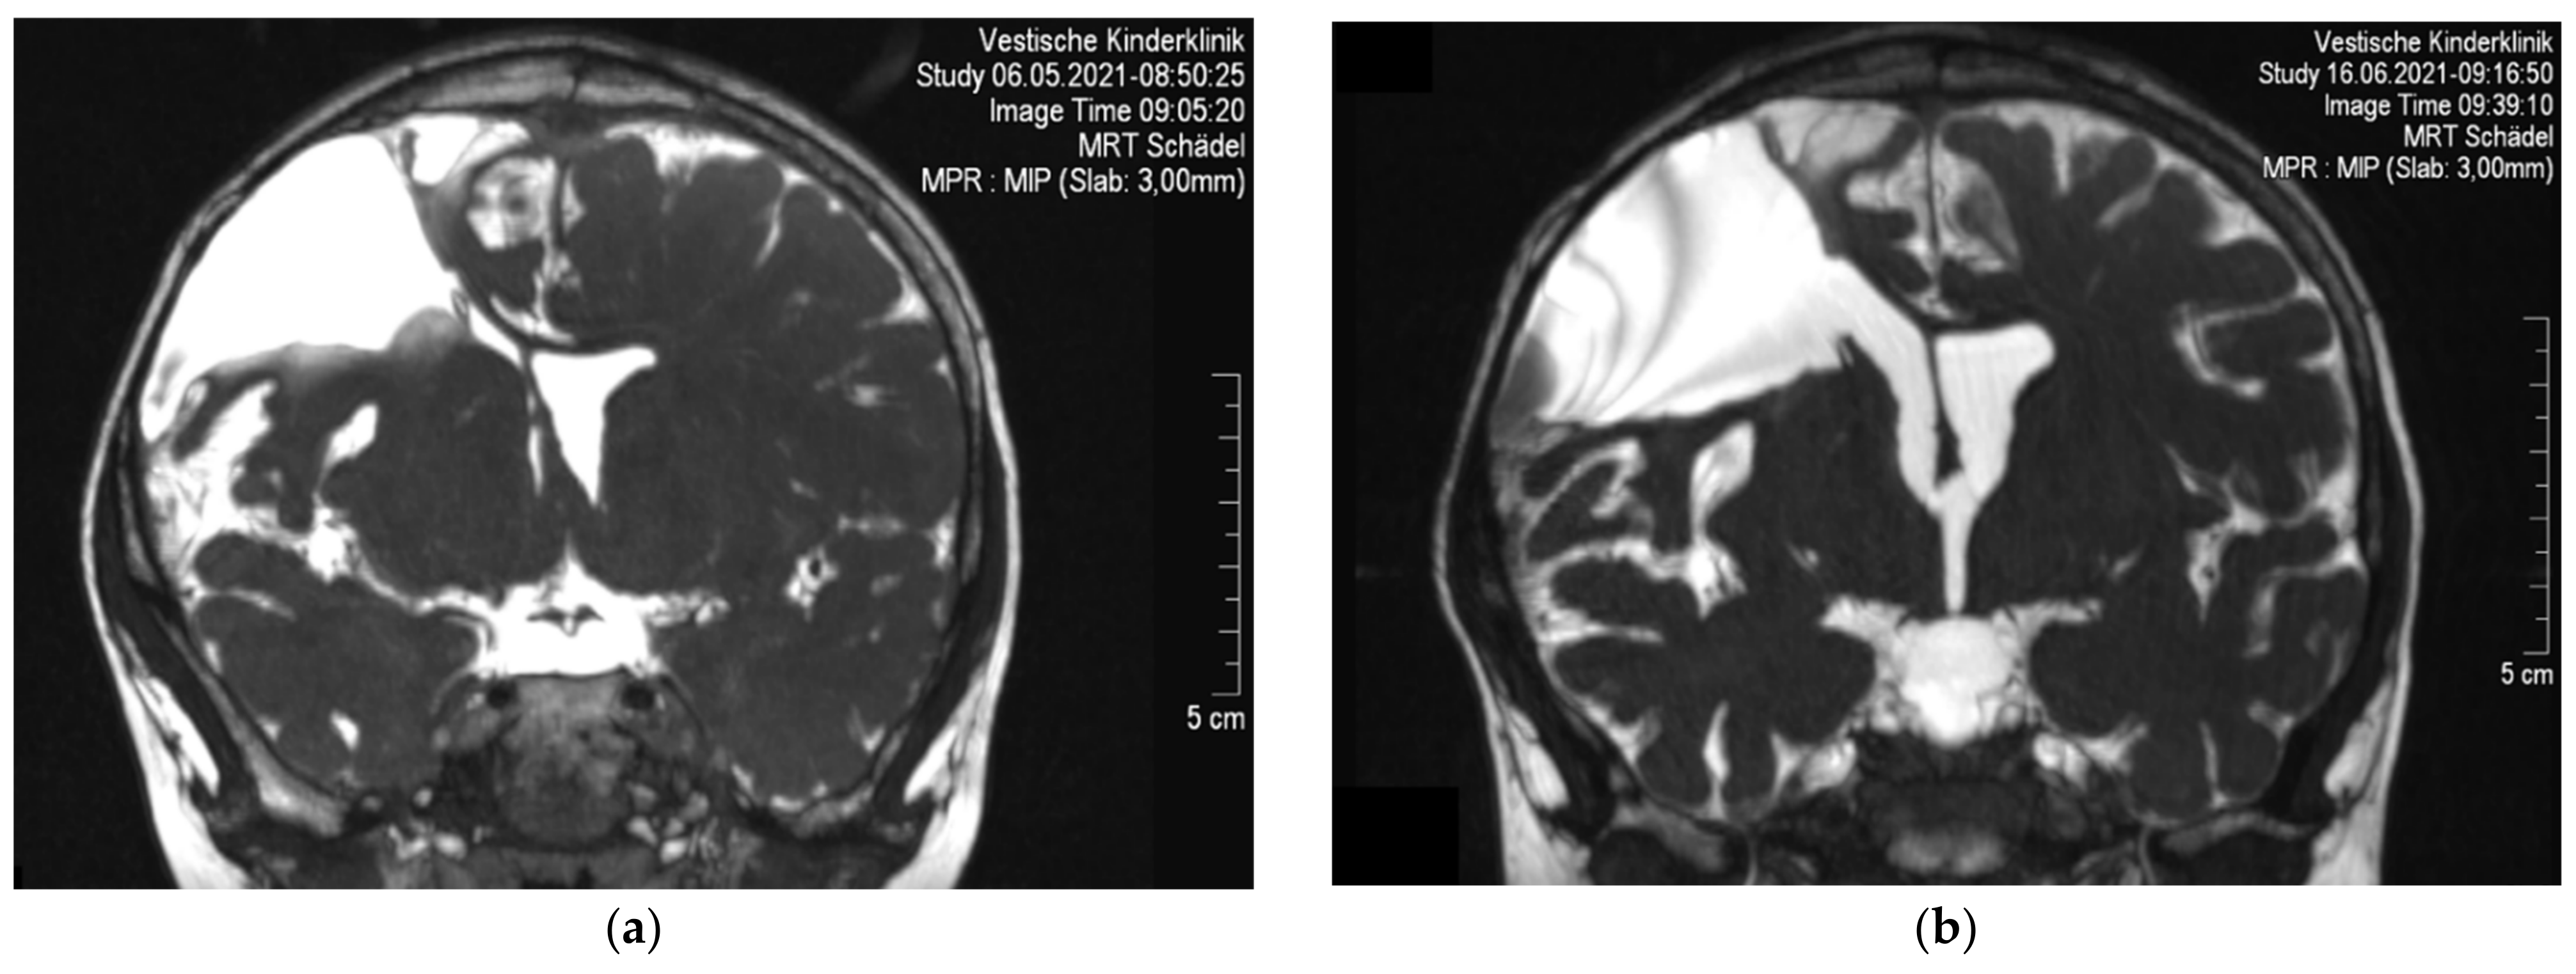

2. Case Report

2.2. Symptoms and Clinical Findings

2.3. Therapeutic Intervention

2.4. Follow-Up and Outcome